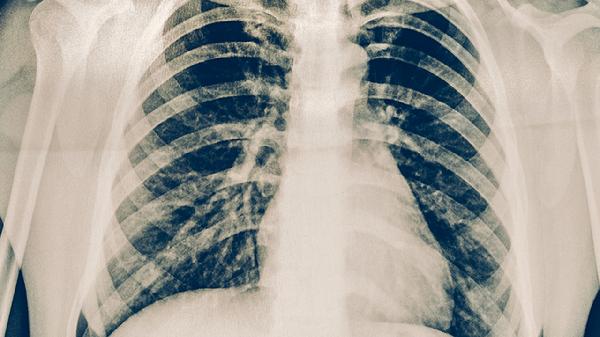

結核病密切接觸者、HIV感染者、糖尿病患者等高風險人群應每年進行胸部X線或結核菌素試驗檢查。出現(xiàn)咳嗽咳痰超過2周、低熱盜汗等可疑癥狀時,需及時進行痰涂片和GeneXpert檢測。潛伏結核感染者可在醫(yī)生指導下預防性服用異煙肼。